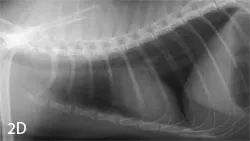

Right lateral (A), left lateral (B), and ventrodorsal (C) thoracic radiographs from a 7-year-old mixed breed neutered male dog. Right lateral (D) and ventrodorsal (E) images from a 4-year-old neutered male domestic shorthair cat. In both cases, the radiographs were deemed normal.